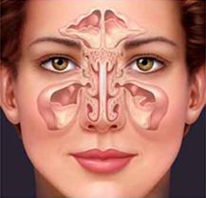

| Polipok az orrüregben és az orrmelléküregben. |

A orrpolip lehet egy- vagy kétoldali, kitölthet egy vagy több orrjáratot, az orrbemenetet, és beterjedhet az orrgaratba, a rostasejtekbe és a melléküregekbe is. A polipok elzárják az arcüregek, a homloküreg kivezető nyílásait is a rostasejtekével egyetemben.

| Polipok az orrüregben és az orrmelléküregben. |

Az orrmelléküregekben a nyálkahártya túlburjánzás elzárja a természetes kivezető nyílásokat, emiatt nem tudnak átszellőzni, ezért gyakori a krónikus arcüreggyulladás, szinte folyamatos a színtelen nyákos vagy gennyes orrváladékozás (nátha), a fejfájás, valamint az orrhangú beszéd.

| Krónikus arcüreggyulladás. |